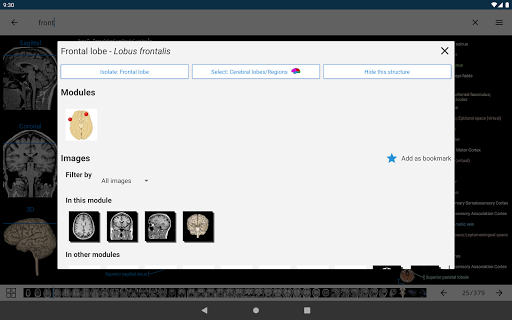

* تحسين عرض التفاصيل للأجزاء التشريحية لتسهيل التعرف عليها في صور الوحدات الحالية والوحدات الأخرى.

* تحسين رؤية تعريفات الأجزاء التشريحية